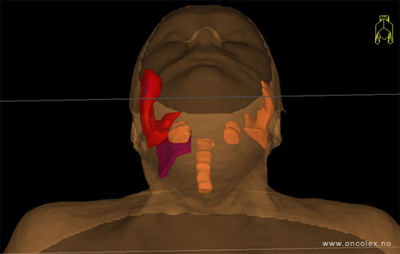

Målvolum

Skisse over hvordan strålefeltet planlegges:

Illustrasjon for målvolum

• GTV (Gross Tumor Volume): Identifisert tumor.

• CTV (Clinical Target Volume) GTV + omkringliggende vev hvor det kan væremikroskopisk spredning.

• ITV (Internal Target Volume): CTV + en indre margin som tar hensyn tilindre bevegelser og endringer av CTV.

• PTV (Planning Target Volume): Innstillingsmargin som inneholder ITV og samtidig tar hensyn til antatte pasientbevegelser, samt variasjoner i pasientopplegging og feltinnstillinger.

• Feltgrense. Tegnes som oftest på kroppen.

ICRU (International Commission on Radiation Units and Measurements)